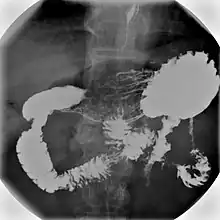

Normal barium swallow fluoroscopic image, showing the ingested barium sulfate being induced down the oesophagus by peristalsis. | |

An upper gastrointestinal series, also called a barium swallow, barium study, or barium meal, is a series of radiographs used to examine the gastrointestinal tract for abnormalities. A contrast medium, usually a radiocontrast agent such as barium sulfate mixed with water, is ingested or instilled into the gastrointestinal tract, and X-rays are used to create radiographs of the regions of interest. The barium enhances the visibility of the relevant parts of the gastrointestinal tract by coating the inside wall of the tract and appearing white on the film. This in combination with other plain radiographs allows for the imaging of parts of the upper gastrointestinal tract such as the pharynx, larynx, esophagus, stomach, and small intestine such that the inside wall lining, size, shape, contour, and patency are visible to the examiner. With fluoroscopy, it is also possible to visualize the functional movement of examined organs such as swallowing, peristalsis, or sphincter closure. Depending on the organs to be examined, barium radiographs can be classified into "barium swallow", "barium meal", "barium follow-through", and "enteroclysis" ("small bowel enema"). To further enhance the quality of images, air or gas is sometimes introduced into the gastrointestinal tract in addition to barium, and this procedure is called double-contrast imaging. In this case the gas is referred to as the negative contrast medium. Traditionally the images produced with barium contrast are made with plain-film radiography, but computed tomography is also used in combination with barium contrast, in which case the procedure is called "CT enterography".[1]

Mechanism

Barium sulfate is swallowed and is a radio opaque substance that does not allow the passage of X-rays. As a result, areas coated by barium sulfate will appear white on an X-ray film. The passage of barium sulfate through the gastrointestinal tract is observed by a radiologist using a fluoroscope attached to a TV monitor. The radiologist takes a series of individual X-ray images at timed intervals depending on the areas to be studied. Sometimes medication which produces gas in the gastrointestinal tract is administered together with the Barium sulfate. This gas distends the gastrointestinal lumen, providing better imaging conditions and in this case the procedure is called double-contrast imaging.[9]